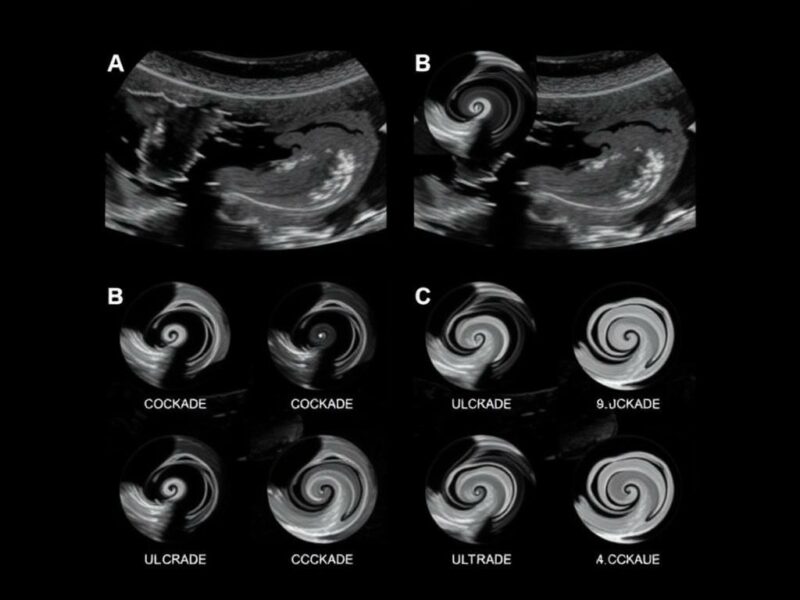

Errores frecuentes al interpretar la «Kokarde»

Es fácil enamorarse del aspecto «bonito» de la diana y suponer que lo que se ve es definitivo. Sin embargo, hay trampas: nódulos linfáticos mesentéricos, asas de intestino en corte transversal inflamada, o incluso un ciego parcialmente plegado pueden simular una «kokarde». Además, la técnica inadecuada, gas intestinal superpuesto o transductores poco adecuados pueden deformar la imagen.

Por eso siempre hay que complementar el hallazgo con la evaluación longitudinal (para confirmar que se trata de una estructura tubular), la compresibilidad, la comparación del diámetro y la búsqueda de otros signos inflamatorios asociados.

La ecografía sigue evolucionando: transductores de mayor resolución, software de mejora de imagen, elastografía y la inteligencia artificial (IA) prometen aumentar la detectabilidad del apéndice y reducir la variabilidad entre operadores. Los algoritmos de IA que señalan zonas de interés y cuantifican parámetros automáticos podrían ayudar especialmente a ecografistas menos experimentados. Además, la tele-ecografía y las plataformas de revisión remota facilitan la consulta en centros con menos experiencia. Aun así, la tecnología no reemplaza la clínica; la combinación de buena técnica, juicio clínico y ayudas tecnológicas será la clave.